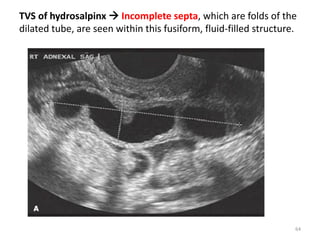

• Sonographic shows:-

 a thin-walled, cystic fusiform structure with incomplete

septa and anechoic contents.

TVS of hydrosalpinx  Incomplete septa, which are folds of the

dilated tube, are seen within this fusiform, fluid-filled structure.